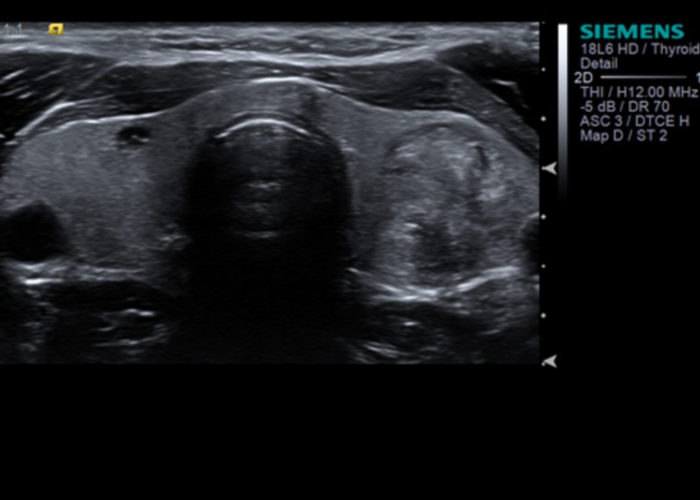

The new Siemens Acuson 300 ultrasound machine employed in Wexford Ultrasound is the latest ultrasound technology from one of the world’s foremost suppliers of medical imaging technology.